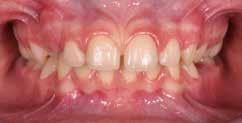

Presentazione del caso > F.V, bambino di cinque anni, presenta una malocclusione di II Classe scheletrica, III Classe dentale molare e canina destra e sinistra, morso inverso anteriore. Le arcate dentali mostrano usura degli elementi dentari anteriori a causa dell’occlusione patologica. Le linee mediane, superiore ed inferiore, sono centrate; il frenulo labiale superiore patologico per un’eccessiva estensione inter-incisale.

Dall’esame clinico si evince la III Classe dentale, l’inversione anteriore e l’over-jet negativo.

Una volta ottenuta la correzione del rapporto molare ed incisale, l’apparecchio elastodontico verrà portato dal paziente solo durante la notte per stabilizzare il risultato ottenuto e guidare l’eruzione degli elementi dentari per un totale di quattordici mesi di terapia. ad inizio trattamento :

Considerazioni > L’analisi cefalometrica ad inizio trattamento dimostra la II Classe scheletrica con protrusione del mascellare superiore e prognazia mandibolare; tendenza alla crescita verticale. L’esame clinico evidenzia una protrusione mandibolare funzionale.